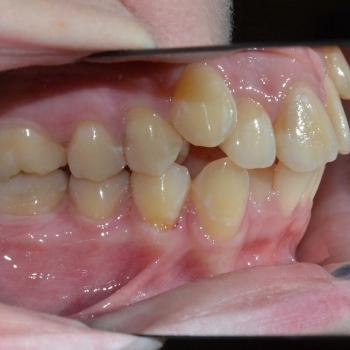

Luca saját elhatározásból, az alsó és felső fogív torlódása, de főleg a két felső szemfog ectopiás helyzete miatt keresett fel. Már elsőre pillantásra látható volt és Luca is sejtette, hogy foghúzások nélkül az Ő esete nem oldható meg,de szerencsére ez nem tántorította el a céljától.

Közös döntés eredményeként fém önligírozó fogszabályozót választottunk, illetve a felső kisőrlők, illetve egy darab alsó metszőfog eltávolítására került sor. Az alsó metszőfog eltávolítása elsőre szokatlannak tűnhet, de a fogszabályozásban ez bevett gyakorlat hiszen esztétikai problémát nem okoz és a húzás által biztosított plusz hely rögtön a megfelelő helyen áll a rendelkezésünkre.